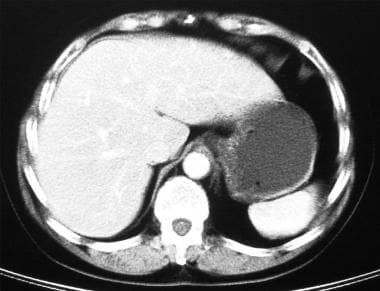

Epidemiology gastric diverticula are rare and c. Weight loss surgery is about reducing your weight and gaining good health. Gastric diverticula are sac like projections that usually originate from the gastric fundus most commonly on the posterior surface. They are the least common of the gastrointestinal diverticula.

Cain jc jordan gl jr comfort mw gray hk. J am med assoc. The gas tric fundus is dened as the portion of the stomach craniad to the gastric car dia. Commonly accompanying this are abnormally dilated short gastric veins which pass from the splenic vein to encircle the gastric fundus and form gastric fundal varices.